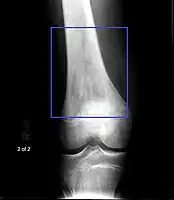

Osteosarcoma of the distal femur

Family physicians and orthopedists rarely see a malignant bone tumor (most bone tumors are benign). The route to osteosarcoma diagnosis usually begins with an X-ray, continues with a combination of scans (CT scan, PET scan, bone scan, MRI) and ends with a surgical biopsy. A characteristic often seen in an X-ray is Codman's triangle, which is basically a subperiosteal lesion formed when the periosteum is raised due to the tumor. Films are suggestive, but bone biopsy is the only definitive method to determine whether a tumor is malignant or benign.

Osteosarcomas tend to occur at the sites of bone growth, presumably because proliferation makes osteoblastic cells in this region prone to acquire mutations that could lead to transformation of cells (the RB gene and p53 gene are commonly involved). Due to this tendency, high incidence of osteosarcoma is seen in some large dog breeds (St. Bernards and Great Danes). The tumor may be localized at the end of the long bone (commonly in the metaphysis). Most often it affects the proximal end of tibia or humerus, or distal end of femur. Osteosarcoma tends to affect regions around the knee in 60% of cases, 15% around the hip, 10% at the shoulder, and 8% in the jaw. The tumor is solid, hard, irregular ("fir-tree," "moth-eaten", or "sun-burst" appearance on X-ray examination) due to the tumor spicules of calcified bone radiating in right angles. These right angles form what is known as a Codman triangle, which is characteristic but not diagnostic of osteosarcoma. Surrounding tissues are infiltrated.